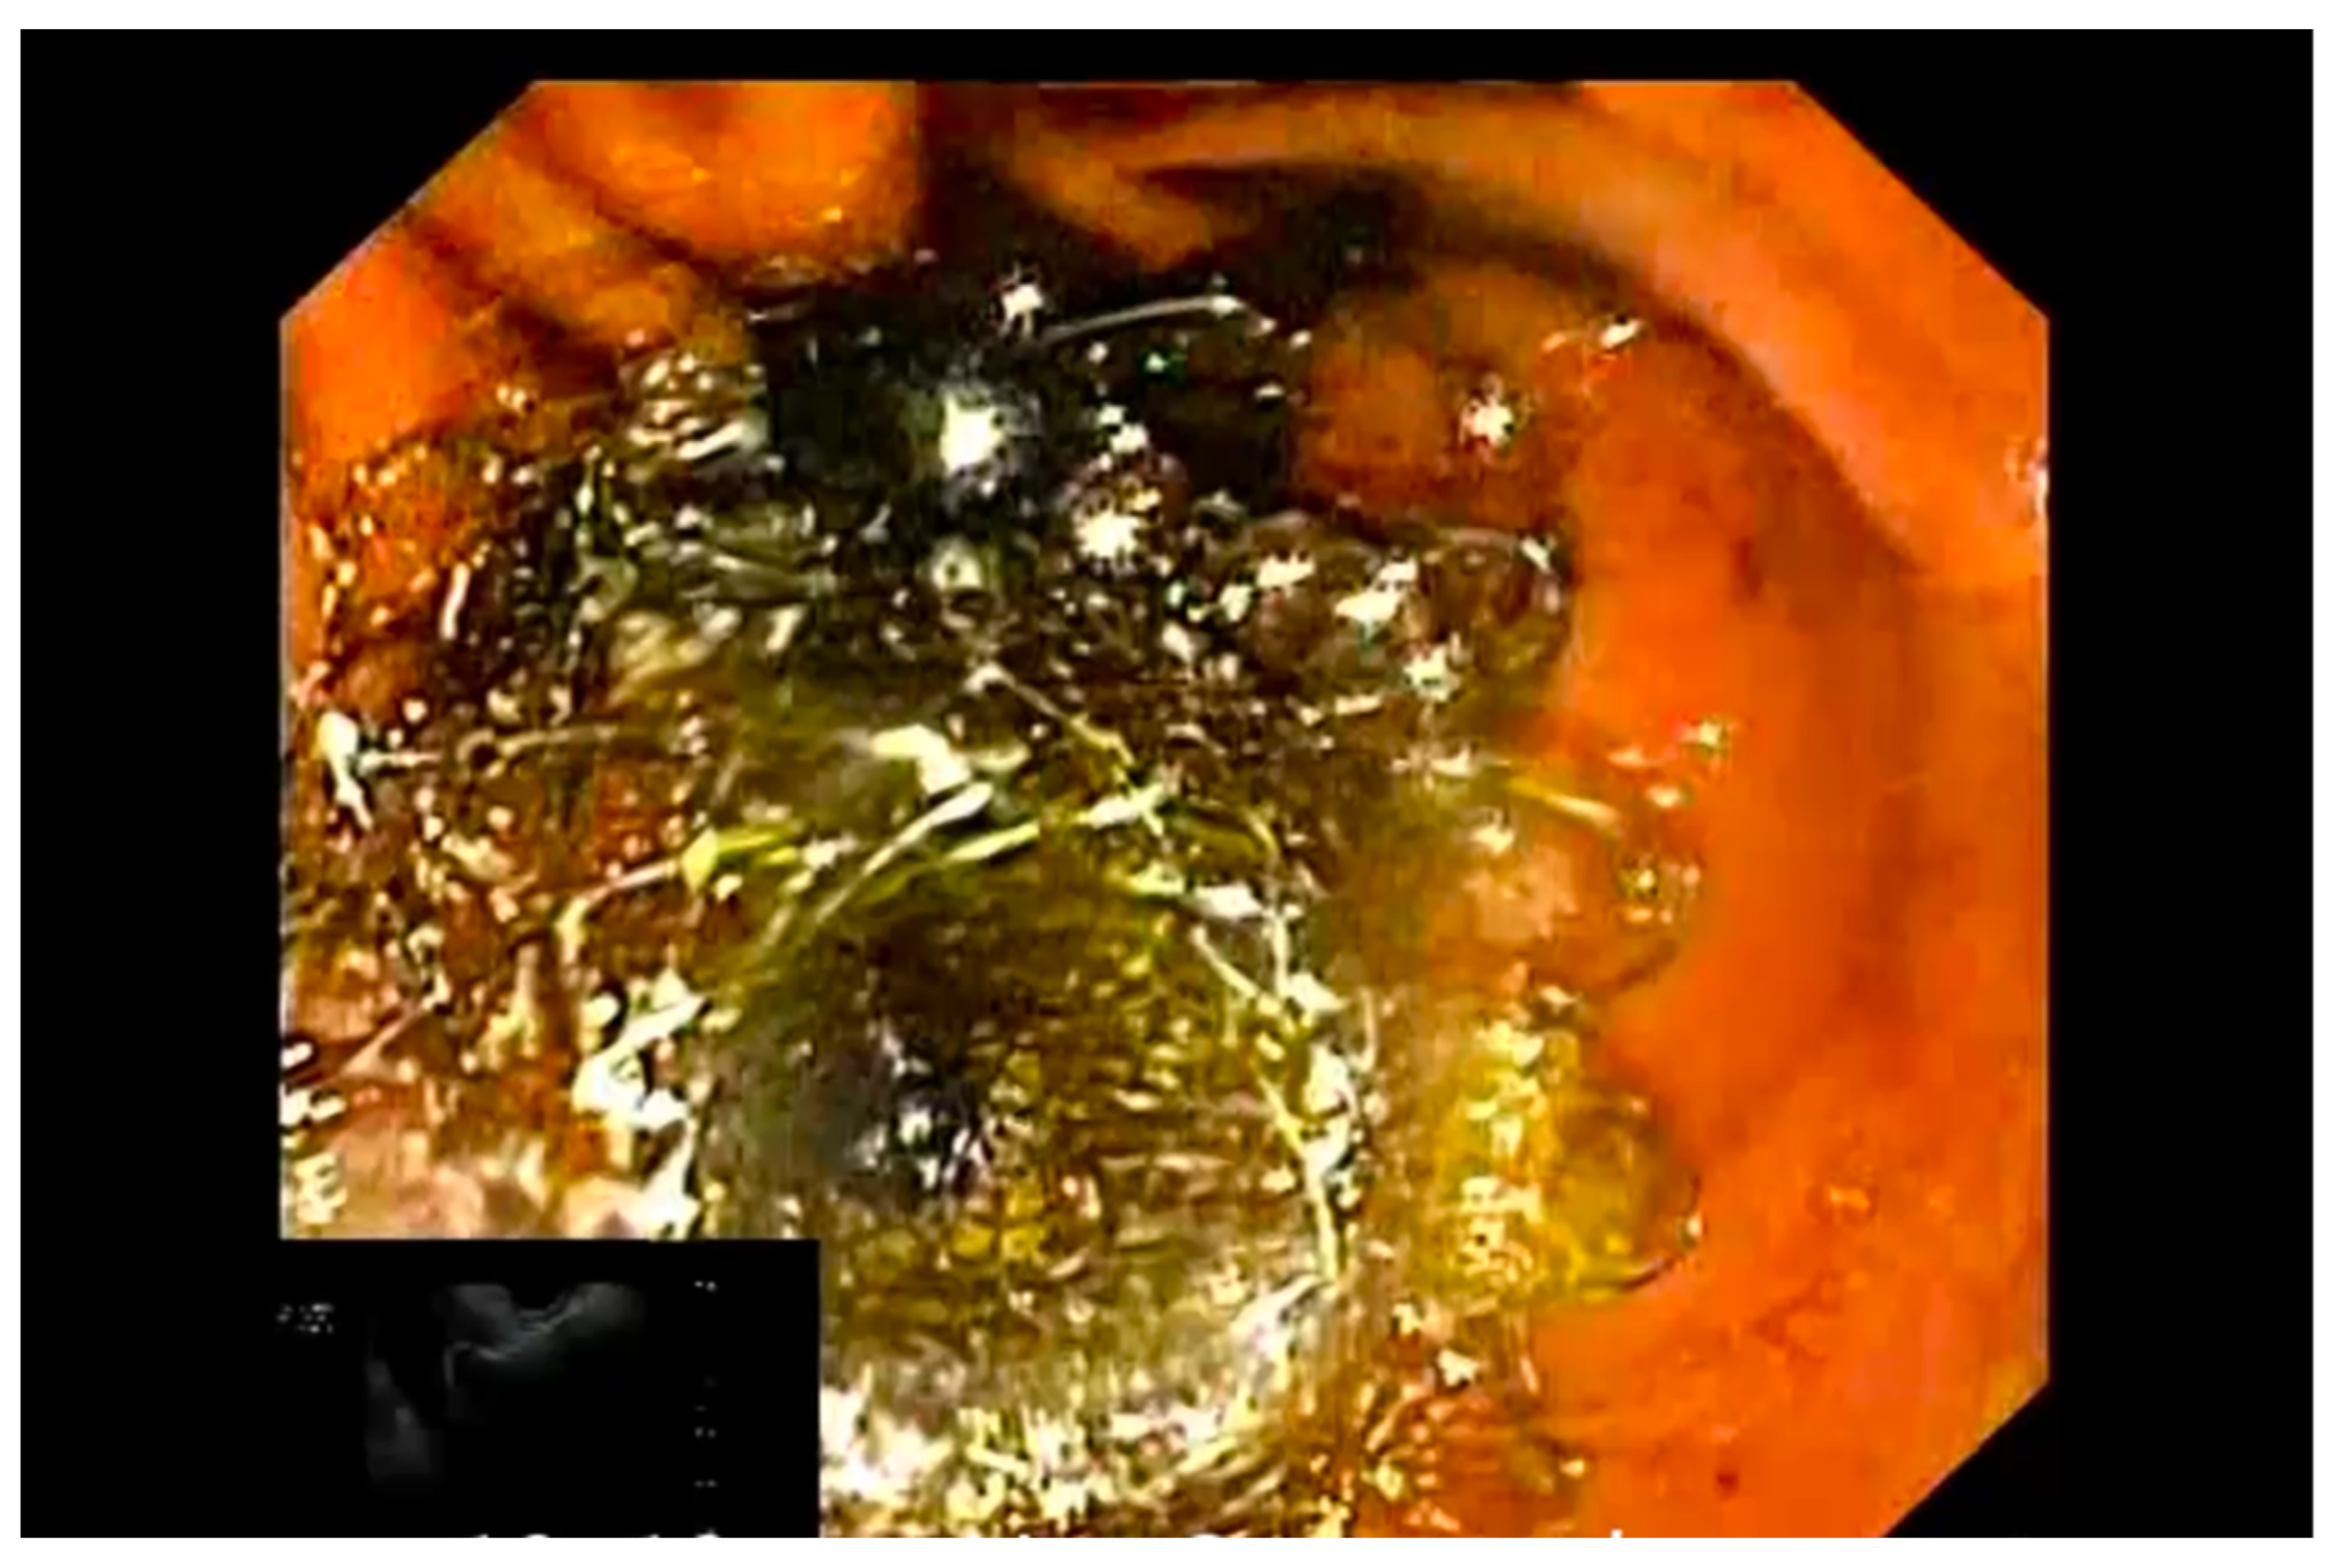

2.2. Study Device

2.3. Procedure

- Chan, S.M.; Teoh, A.Y.B.; Yip, H.C.; Wong, V.W.Y.; Chiu, P.W.Y.; Ng, E.K.W. Feasibility of per-oral cholecystoscopy and advanced gallbladder interventions after EUS-guided gallbladder stenting (with video). Gastrointest. Endosc. 2017, 85, 1225–1232. [Google Scholar] [CrossRef]

- Mangiavillano, B.; Moon, J.H.; Crinò, S.F.; Larghi, A.; Pham, K.D.-C.; Teoh, A.Y.B.; Paduano, D.; Lee, Y.N.; Yoo, H.W.; Shin, I.S.; et al. Safety and efficacy of a novel electrocautery-enhanced lumen-apposing metal stent in interventional EUS procedures (with video). Gastrointest. Endosc. 2022, 95, 115–122. [Google Scholar] [CrossRef]

- Mangiavillano, B.; Auriemma, F.; Bianchetti, M.; Repici, A. A cholecystoduodenostomy with a new type of lumen-apposing metal stent. Dig. Liver Dis. 2021, 53, 1203. [Google Scholar] [CrossRef]